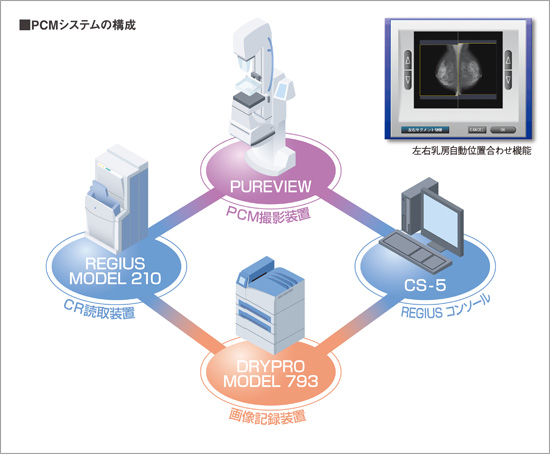

コニカミノルタでは位相コントラスト技術を活用したデジタル乳房X線撮影システムを開発。PCMシステムとしてデビューいたしました。

PCMシステムは、PCM用半切カセッテによる撮影と43.75μm読み取りにより、約7000万画素もの超高密度な画像データーを取得します。さらにフィルム出力時の原寸出力と最高濃度4.0フィルムの組み合わせにより、高い鮮鋭性と粒状性を兼ね備えた最高画質を実現しています。